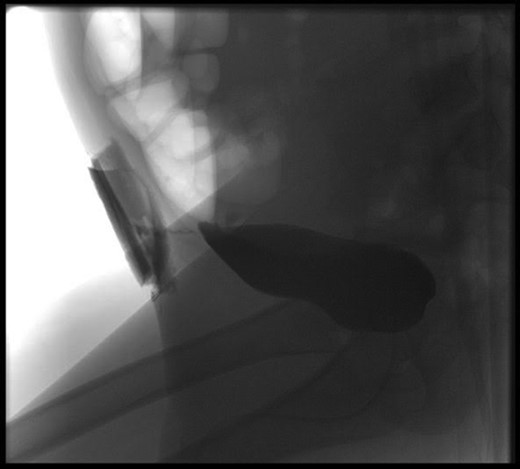

At our centre, a size 6fr catheter was inserted and kept on free drainage. The suprapubic drain was removed as the urine was leaking around the tube rather than through it, and an absorbent dressing placed over the port site wound prior to further investigations. A cystogram performed via the indwelling Foley catheter showed tracking of contrast to the abdominal wall, soaking the overlying dressing (Fig. 1). There was no free intraperitoneal leak of contrast. These findings were consistent with an extra peritoneal bladder injury.

Cystogram showing tracking of contrast to the abdominal wall, and soaking the overlying dressing.